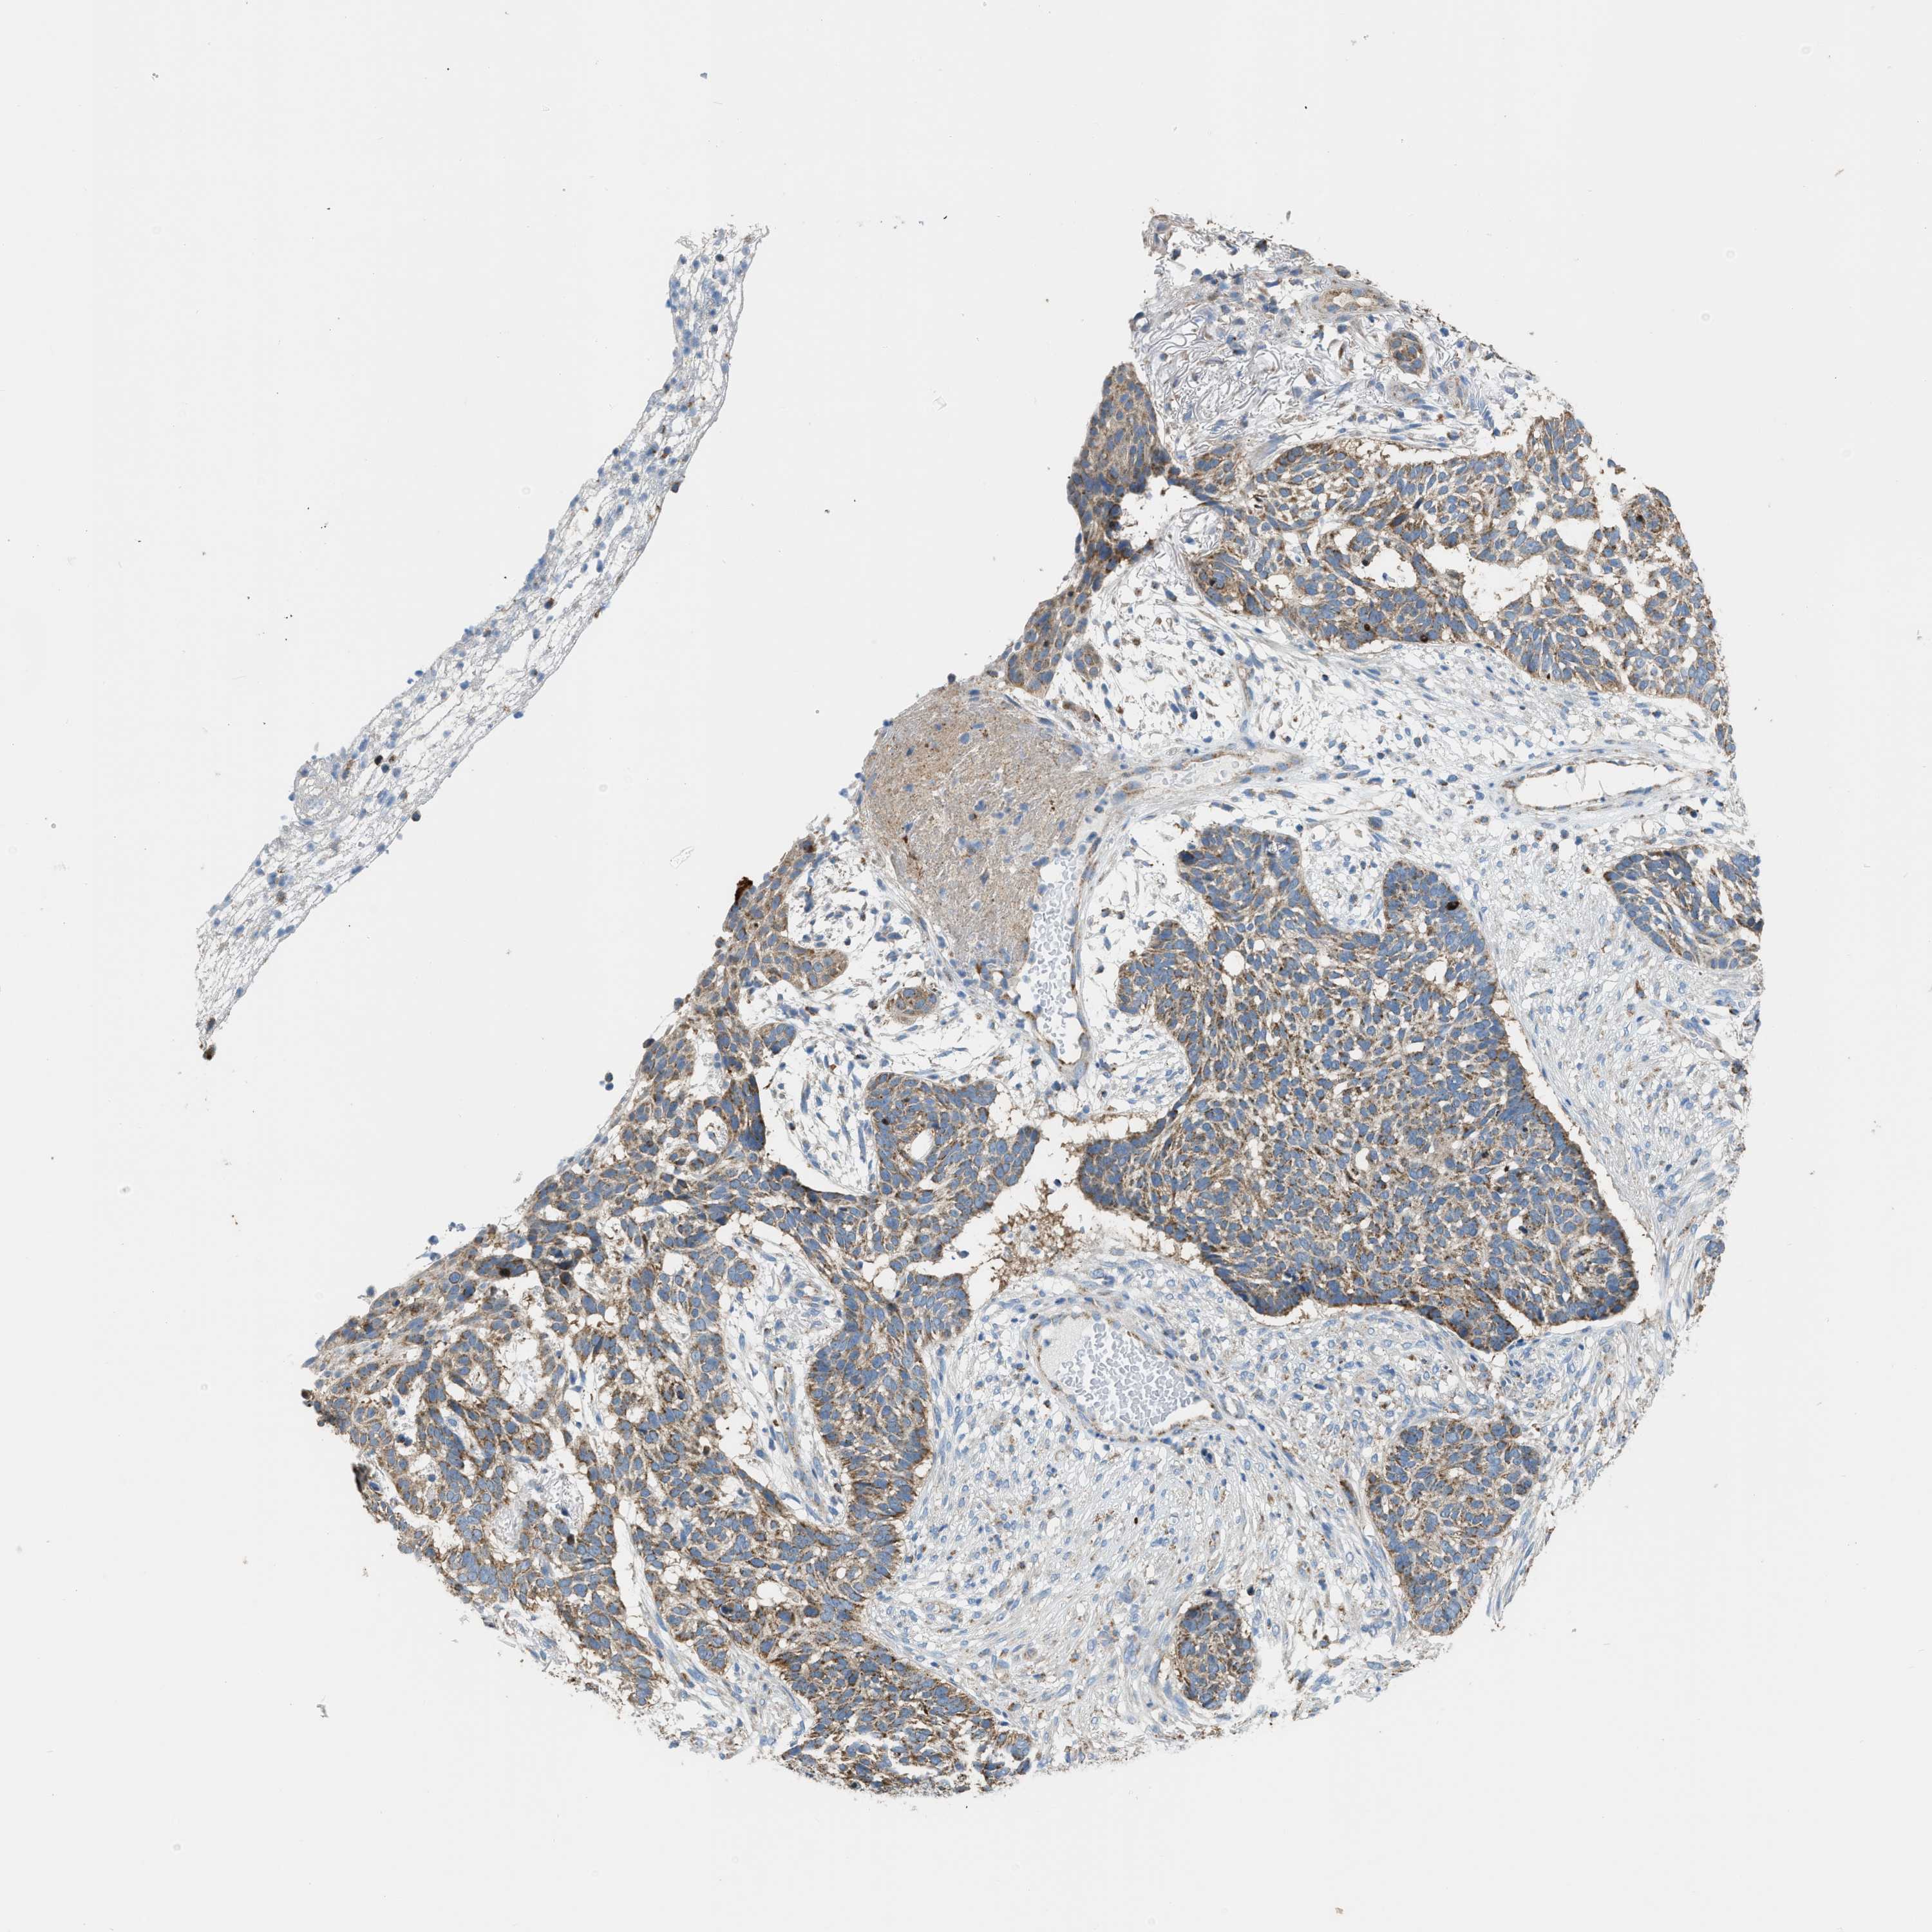

SKIN CANCER - Protein expressioni

A mouse-over function shows sample information and annotation data. Click on an image to view it in a full screen mode. Samples can be filtered based on level of antibody staining by selecting one or several of the following categories: high, medium, low and not detected. The assay and annotation is described here.

Each image is clickable and will lead to virtual microscopy that enables deeper exploration of all samples and also displays staining intensity scores, fraction scores and subcellular localization as well as patient and tissue information for each sample.

Antibody HPA018910

Basal cell carcinoma